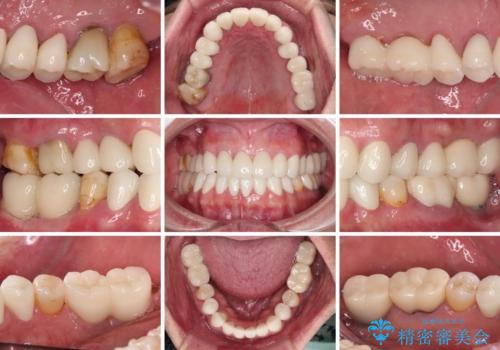

憧れの白い歯に 全顎セラミック治療

抜歯が必要な奥歯は、インプラント並びにブリッジにより補綴を行い、上下前歯は反対咬合を改善させるように補綴治療を行うこととしました。

健全な歯を削ってセラミッククラウンに置き換えることは、本来避けるべき治療と考えますが、今回は①患者様が60歳を越えていること、②要改善の咬合により抜歯が必要な奥歯があること、③反対咬合の前歯改善の手段としてセラミック治療が選択肢にあることなどから、全顎的なセラミック治療を行うこととしました。